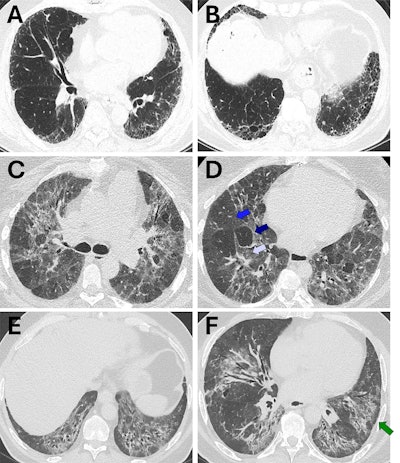

Representative cases of usual interstitial pneumonia (UIP), fibrotic hypersensitivity pneumonitis (fHP), and nonspecific interstitial pneumonia (NSIP) for which there was concordance between guideline-defined pattern (strict adherence to guidelines) and radiologist-assigned pattern (radiologist expert opinion). (A, B) Axial CT images show a case that met the criteria for guideline-defined typical UIP (2,3) and was also assigned UIP by the radiologist. The distribution is basal and peripheral, with the presence of honeycombing and reticulation and no substantial ground-glass opacity. There are no other findings that are incongruent with UIP. (C, D) Axial CT images show a case that met the criteria for guideline-defined typical fHP (2,3) and was also assigned fHP by the radiologist. The distribution is mid-upper in the craniocaudal plane and both peripheral and central in the axial plane. There is no honeycombing, but there is substantial reticulation and traction bronchiectasis. There is both lobular ground-glass opacity (white arrow in D) and hypoattenuating lung (dark blue arrow in D) alongside normal lung (blue arrow in D), forming a three-density sign. There are no other findings that are incongruent with fHP. (E, F) Axial CT images show a case that met the criteria for guideline-defined typical NSIP, defined using the 2008 American Thoracic Society workshop report (9), and was also assigned NSIP by the radiologist. The distribution is basal in the craniocaudal plane and both peripheral and central in the axial plane, with a prominent element of subpleural sparing (arrow in F). There is substantial ground-glass opacity, both pure and admixed with fibrosis. There are no other findings that are incongruent with NSIP.Representative cases of usual interstitial pneumonia (UIP), fibrotic hypersensitivity pneumonitis (fHP), and nonspecific interstitial pneumonia (NSIP) for which there was concordance between guideline-defined pattern (strict adherence to guidelines) and radiologist-assigned pattern (radiologist expert opinion). (A, B) Axial CT images show a case that met the criteria for guideline-defined typical UIP (2,3) and was also assigned UIP by the radiologist. The distribution is basal and peripheral, with the presence of honeycombing and reticulation and no substantial ground-glass opacity. There are no other findings that are incongruent with UIP. (C, D) Axial CT images show a case that met the criteria for guideline-defined typical fHP (2,3) and was also assigned fHP by the radiologist. The distribution is mid-upper in the craniocaudal plane and both peripheral and central in the axial plane. There is no honeycombing, but there is substantial reticulation and traction bronchiectasis. There is both lobular ground-glass opacity (white arrow in D) and hypoattenuating lung (dark blue arrow in D) alongside normal lung (blue arrow in D), forming a three-density sign. There are no other findings that are incongruent with fHP. (E, F) Axial CT images show a case that met the criteria for guideline-defined typical NSIP, defined using the 2008 American Thoracic Society workshop report (9), and was also assigned NSIP by the radiologist. The distribution is basal in the craniocaudal plane and both peripheral and central in the axial plane, with a prominent element of subpleural sparing (arrow in F). There is substantial ground-glass opacity, both pure and admixed with fibrosis. There are no other findings that are incongruent with NSIP.RSNA